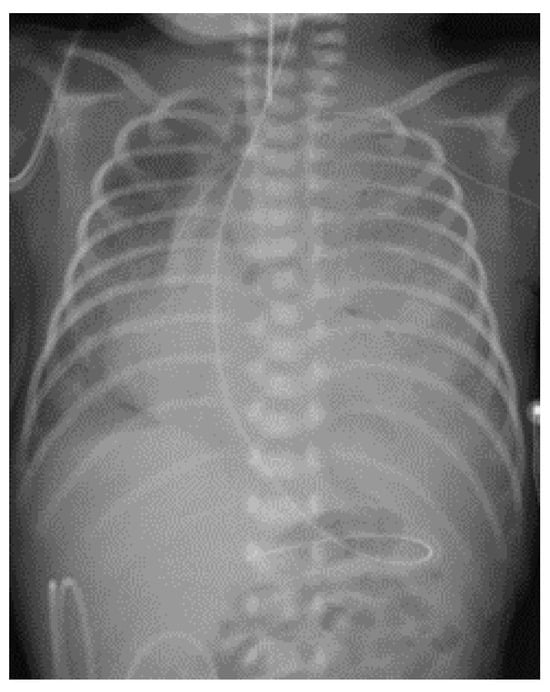

2. Case Presentation